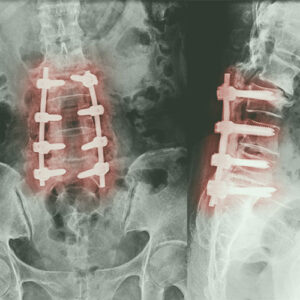

Ernia del Disco